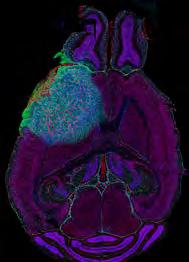

Image: Microscopic image of the ductal tree of the mouse mammary gland

Credit: Hendrik Messal and Jacco van Rheenen

Answering this question by developing novel models and optimising existing models of DCIS is a major component of the team’s ambitious programme, which is being spearheaded by co-investigators Jos Jonkers, Jacco van Rheenen and Fariba Behbod. Many of these models have now been shown to be reliable, realistic tools for studying the progression of human DCIS. For example, the Mouse INtraDuctal (MIND) model – in which patients’ DCIS epithelial cells are injected into mouse mammary glands and observed as they progress naturally – has recently been reported to accurately mimic all histological subtypes of human DCIS.

The team is now able to visualise the entire mammary gland through in vivo models such as MIND, as enabled by the development of a workflow incorporating 3D imaging and intravital microscopy –a powerful tool for imaging biological processes in live animals. This technology is already revealing new information about the growth patterns and ductal architecture in indolent and invasive disease.